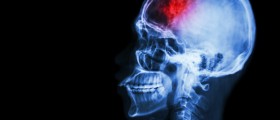

Hello, I am 45 years old and I have been suffering from migraine for the past 6 months. It seems that I have got this problem along with the other menopausal symptoms. And a friend of mine tells me that the stroke risk is greater for the migraine sufferers. Is that really how it is?

I have heard that some doctors think that the migraine begins with the constant changing of the vasoconstriction and vasodilatation in the patient’s brain. This means that there might be some chance for the increased risk, and it is about two times higher than in people with no migraine. And also, some medications used for migraine might additionally increase that possibility.